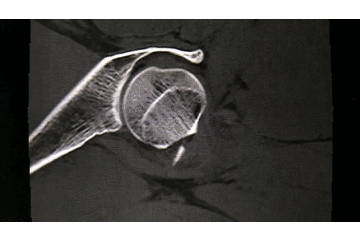

7. 摆 4 字位检查侧位导针的位置是否恰当

笔者的部分股骨颈骨折病例在牵引床被占用的情况下,会选择在普通手术床完成手术,所以必须打上三枚克氏针后再摆 4 字位透视侧位